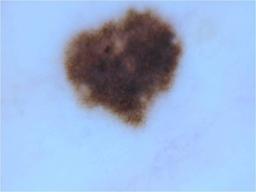

{

"age_approx": 30,

"anatom_site_general": "anterior torso",

"concomitant_biopsy": false,

"diagnosis_1": "Benign",

"diagnosis_2": "Benign melanocytic proliferations",

"diagnosis_3": "Nevus",

"diagnosis_4": "Nevus, Atypical, Dysplastic, or Clark",

"diagnosis_5": "Nevus, Dysplastic",

"image_type": "dermoscopic",

"melanocytic": true,

"sex": "female"

}